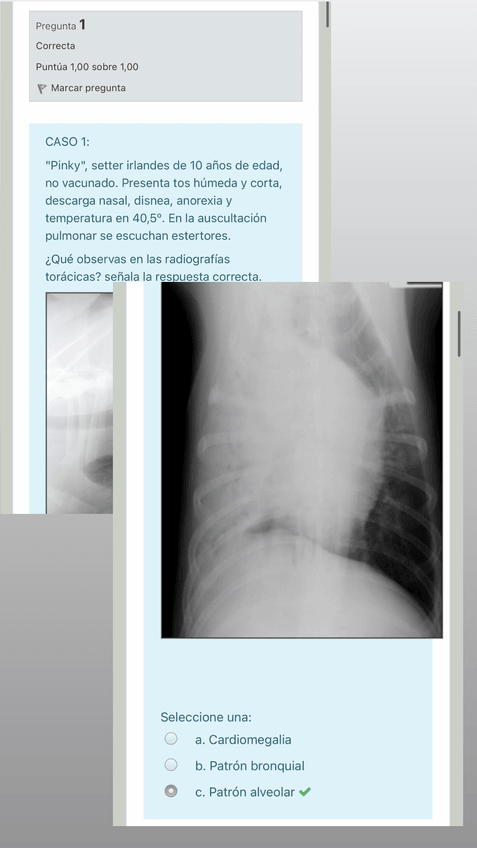

Test Práctica 7 Prope!

He publicado nuevos apuntes de 3º Propedéutica Clínica: Test Práctica 7 Prope!